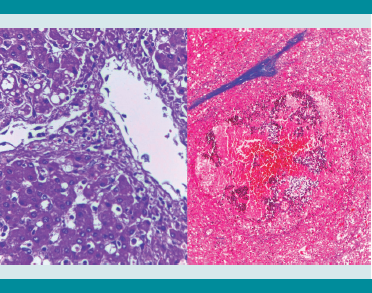

El cuadro final de este paciente parece haber sido una septicemia de origen probable en un cuadro enteral y que lo condujo a un choque séptico. Los cambios microscópicos en intestino son poco expresivos, como suele suceder en muchas infecciones bacterianas agudas; encontramos hiperplasia linfoide y cambios regenerativos en las criptas de yeyuno e íleon, pero las huellas de la septicemia y choque séptico son evidentes. Tenemos una hepatitis séptica y una esplenitis séptica con hiperemia masiva (Figuras 5 y6), hay hemofagocitosis en hígado y en médula ósea, una colitis hemorrágica segmentaria en ángulo esplénico (Figura 7) y evidencia de una catástrofe circulatoria y de perfusión tisular con una necrosis cortical renal y trombos de fibrina en glomérulos renales.